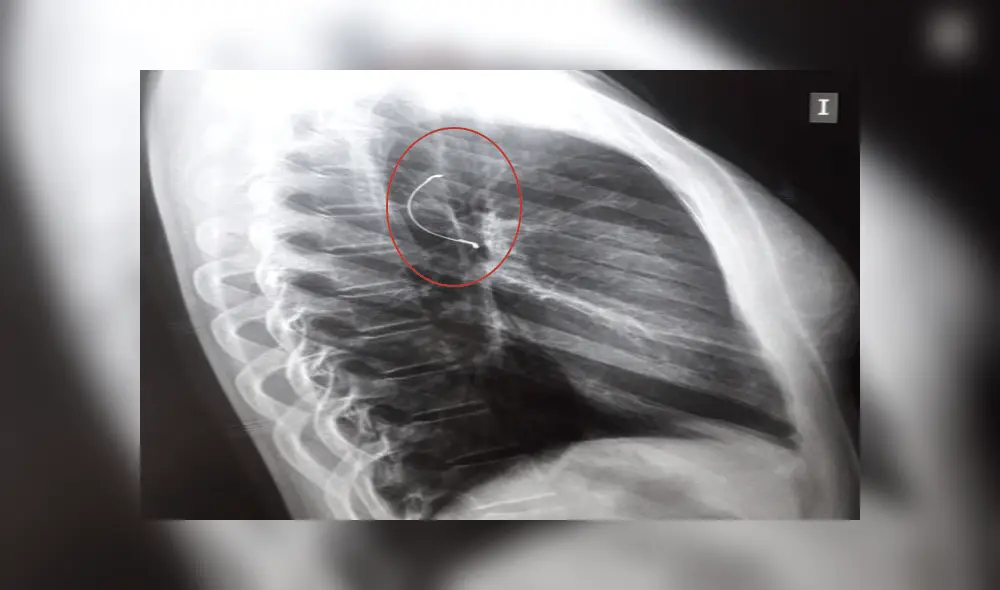

Radiografía de tórax de la menor.

Sin embargo, cuando las esperanzas se estaban acabando, la joven vomitó y el objeto subió hasta su garganta, tras esta acción los médicos realizaron una nueva radiografía y dijeron que con una endoscopia podrían sacar el expansor.

La menor fue sometida al proceso quirúrgico y la operación salió exitosa. Actualmente, se recupera favorablemente en el Instituto Nacional de Enfermedades Respiratorias y del Ambiente Juan Max Bohener (Ineram) luego de ser sometida al procedimiento el pasado lunes por la mañana.